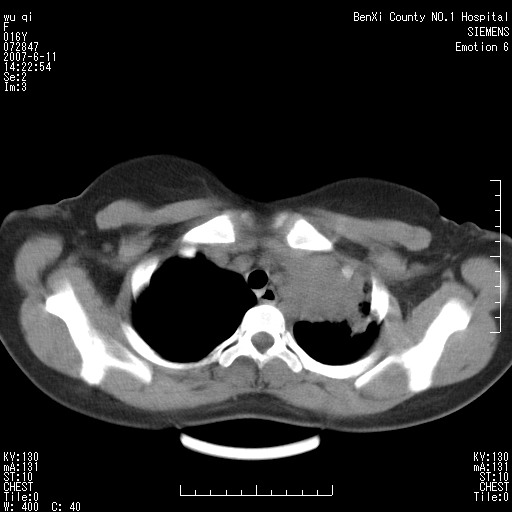

女.16、咳嗽、乏力、消受,食欲差,一个月余,无咯血,一个月前有发热。经抗炎治疗发热消失,仍咳嗽。平扫ct值34-45hu,增强后60-78hu明显强化,另外为了大家方便阅片,简单提下自己意见,纵隔内淋巴结肿大,左肺片影,其内密度不均,增强扫描明显强化,左肺上叶支气管可见支气管气象。尖段闭塞。冠状位可见左侧锁骨下静脉受压下移。请大家会诊,分析。

其实这个病例平扫我和大家的诊断一样,考虑为肺结核,加上相似的症状。增强后我发现原来左侧的锁骨下静脉受压下移,

1。所以能不能就是肺外的病变呢?并且是实性的肿物。只有肺外的实性病变可以把锁骨下静脉压迫到如此地步?当然,结核可以粘联,可是谁见过结核如此可怕的牵拉作用,累及到肺外大血管了。

不知道大家为什么一口同声的赞同肺结核的诊断,有依据么?就算结核可及理解?那么支气管内膜结核怎么样解释,我并未见上叶主支气管有移行性狭窄。只能说上叶支气管受压下移,开口略向外。

在请问大家,左上叶支气管未见狭窄,顶多尖段闭塞,怎么会有如此大片的肺不张?就算是肺不张也顶多是一个小的尖段不张。再说请问大家看见代偿性气肿了么?

5。结核有强化可以理解,但是如此明显的强化,平扫ct值34-45hu,增强后60-78hu明显强化。局限于左肺的大片状病灶解释的通么?